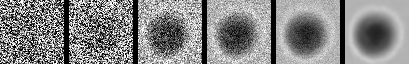

Image Generation. The image generation process begins with a sample of pure random Gaussian noise, denoted as . The goal is to progressively reverse the noising process, step by step, using the learned model to generate a realistic image. As shown in Figure 2, the model applies the learned denoising process starting from the random noise, iteratively refining the noisy image at each step to reconstruct the original data distribution.

At each step , the model predicts the denoised data from the noisy data by sampling from the learned distribution , as defined in the reverse process. This process continues until , at which point the generated data is a sample from the target distribution, resembling a clean image. The final result is an image that was generated from random noise, having gone through a series of denoising steps, guided by the reverse diffusion process learned during training.

Figure 2 provides a visualization of the denoising process in the reverse diffusion trajectory. Starting from pure Gaussian noise, the model progressively refines the image over 1,000 steps in our setup, gradually introducing particle-specific structures in a visually interpretable manner. To illustrate this process, we present six representative images along the trajectory. This progression highlights the ability of the generative model to recover subtle class-specific features, such as the halo effect in air bubbles or the smooth texture in silicone oil droplets, reinforcing confidence in the utility of these samples for downstream classification.